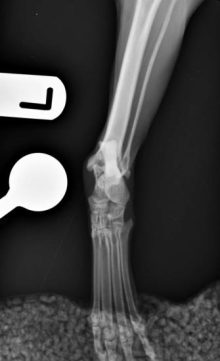

Treatment of a radius and ulna fracture in a Whippet

By Eastcott Referrals Orthopaedic Surgeon Fabio Frazzica A 1-year-old female Whippet presented with a distal diaphyseal, simple, transverse, closed ...